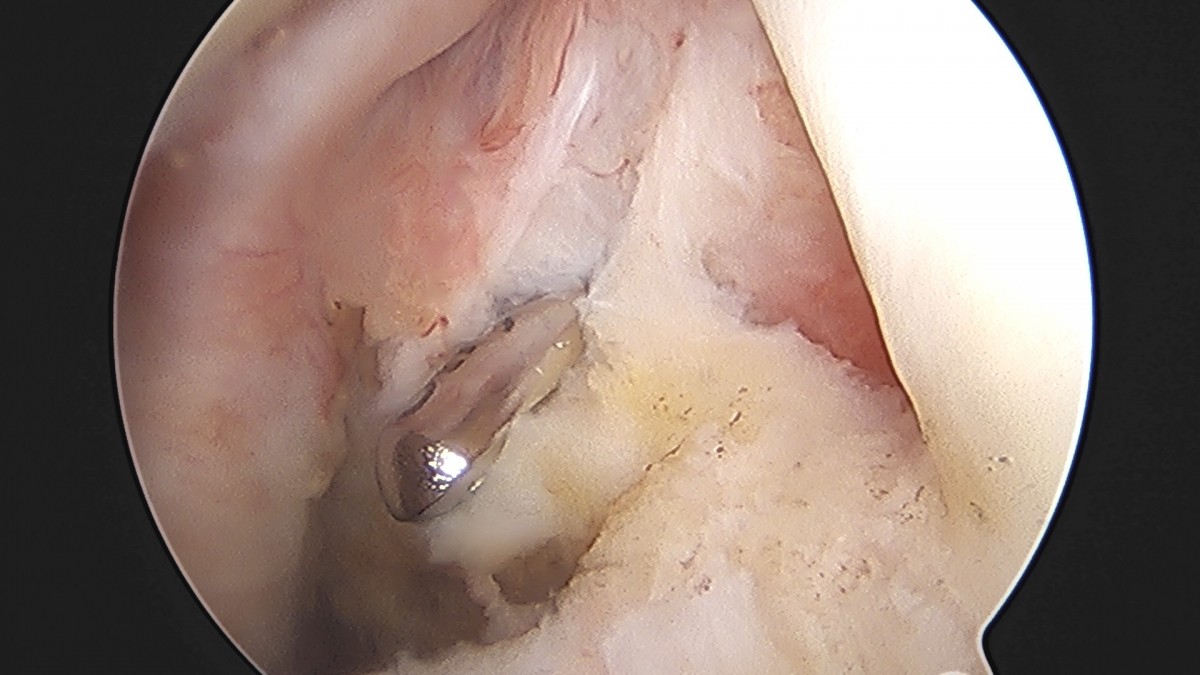

이재상원장님 어깨 견봉하 감압술 및 관절낭 이완술 음성O 환자

작성자 최고관리자 댓글 0건 조회 805회 작성일 25-09-16 15:32